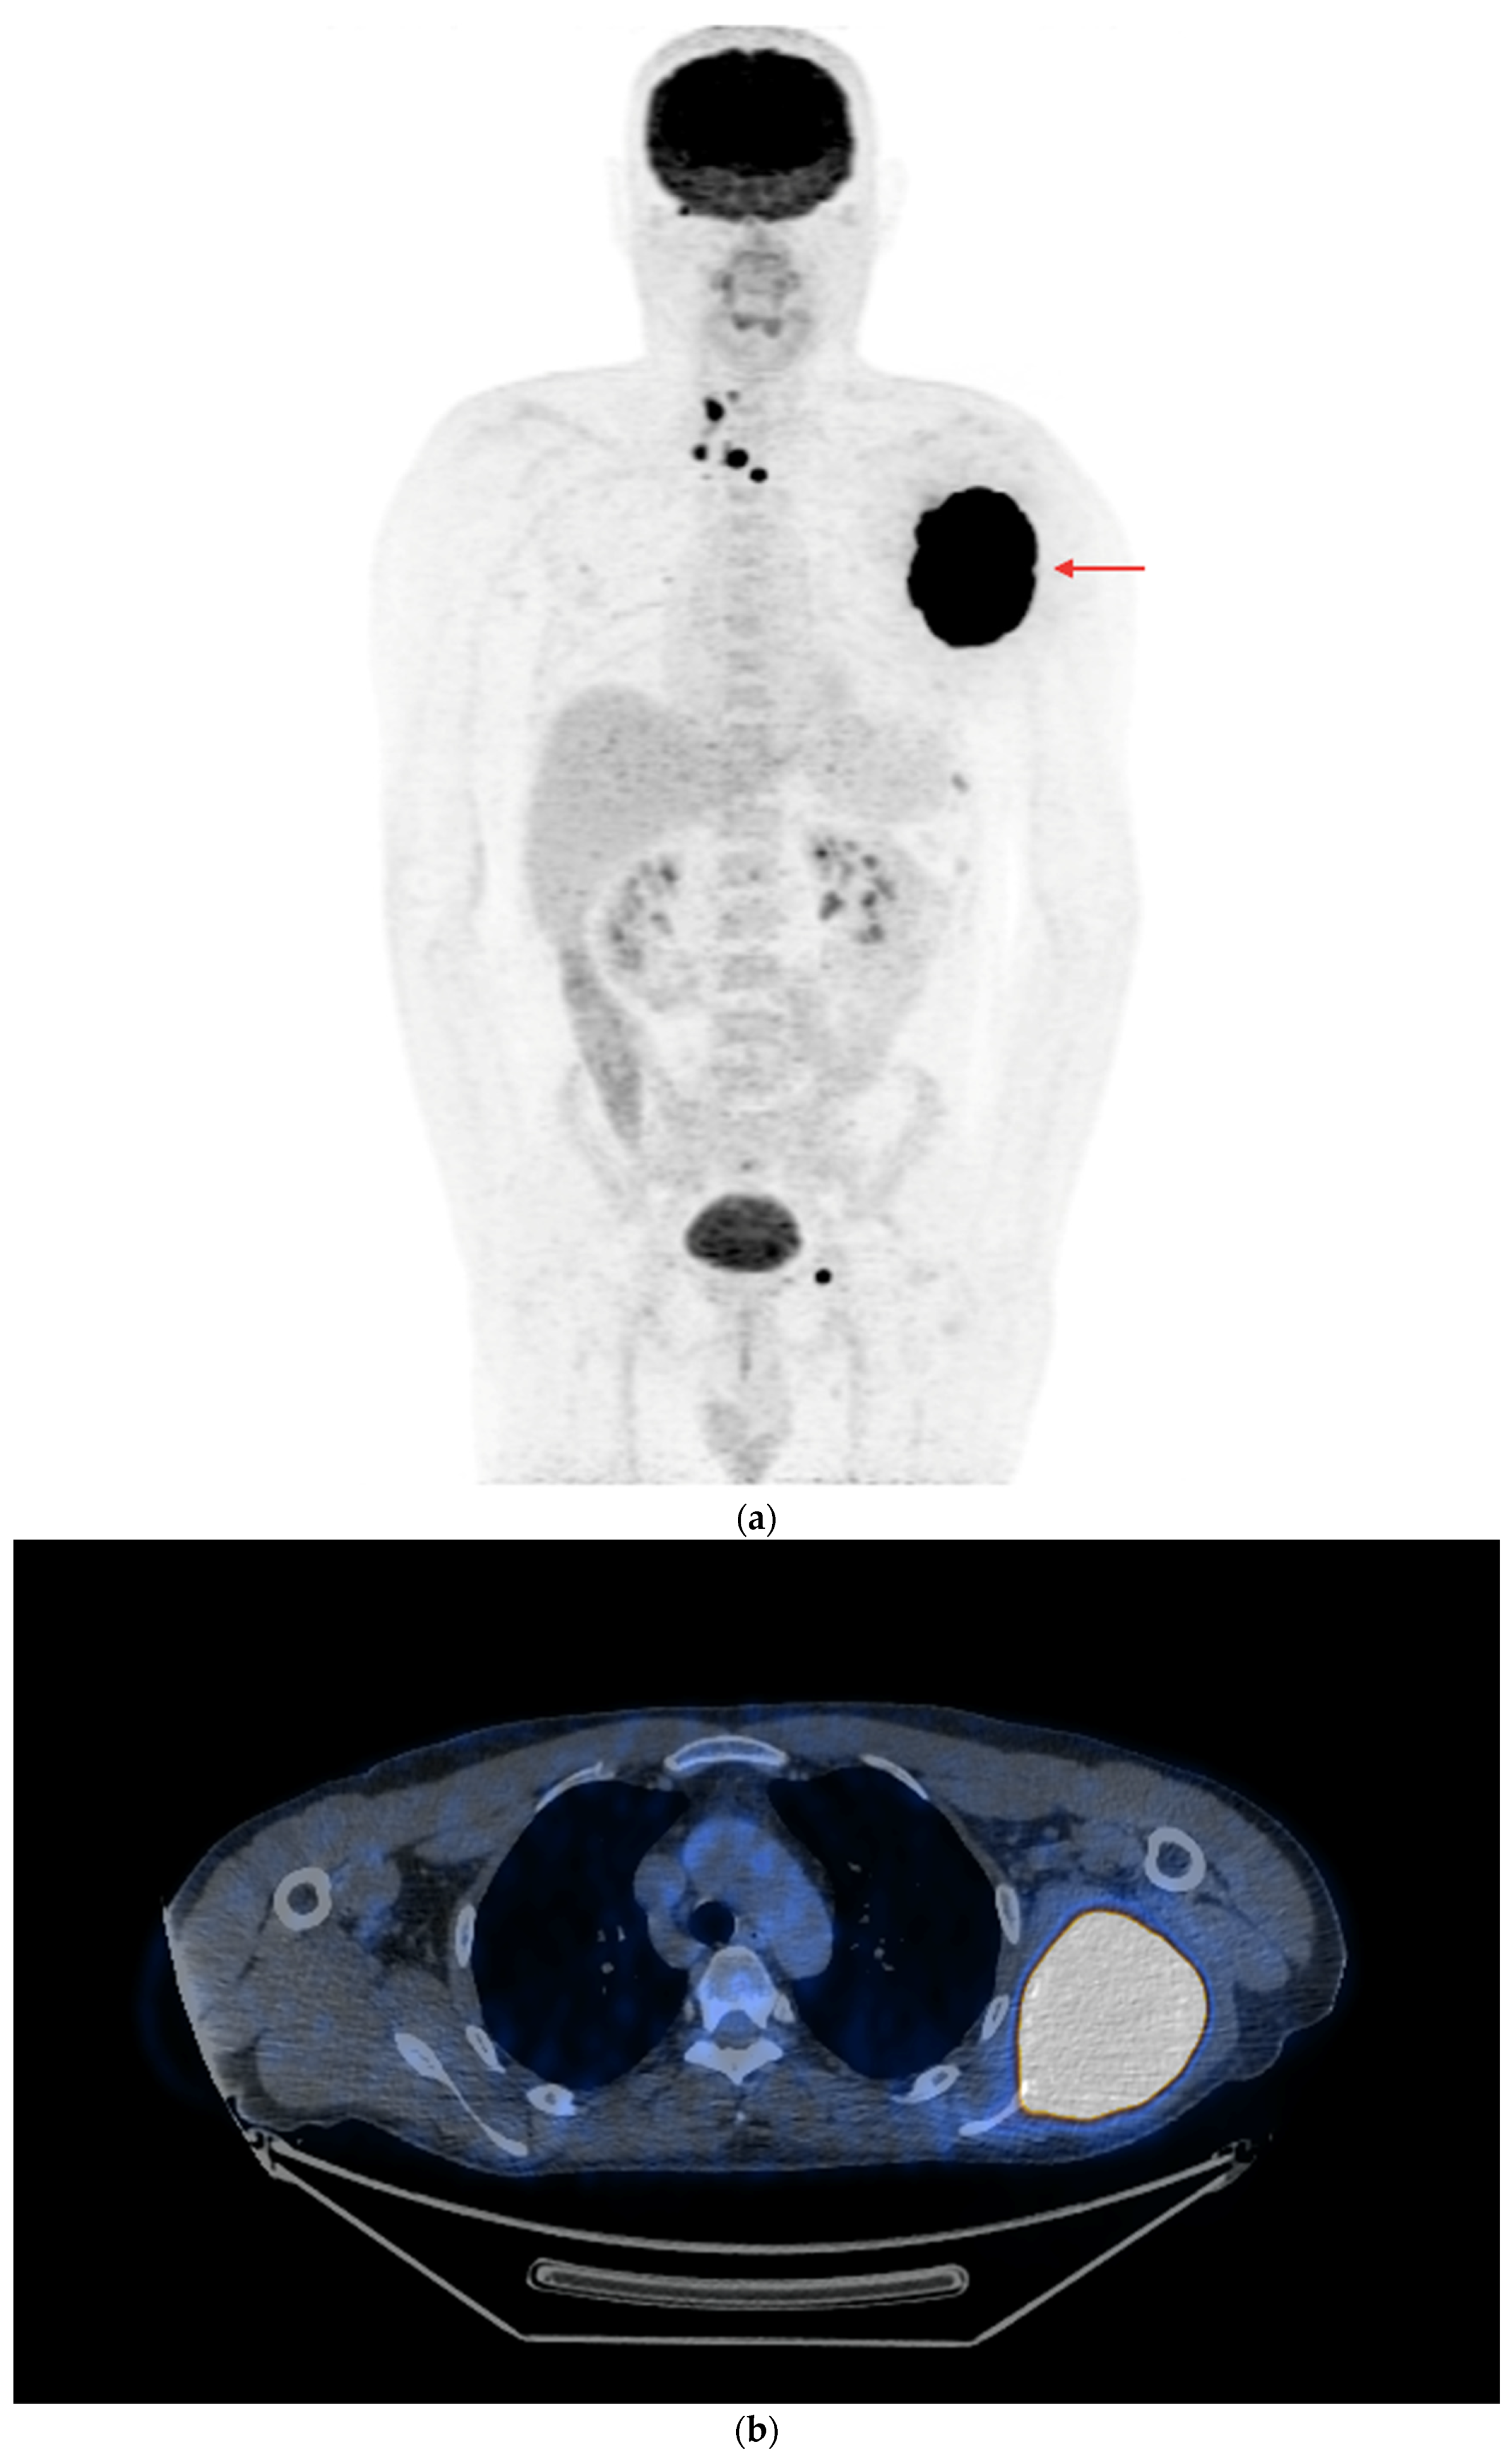

- In the case of potentially resectable lesions, the lesions were operated on after the FNA verification (Figure 3a,b).

Figure 3. PET/CT with [18F]FDG (a) Maximum-intensity projection (MIP). (b) Axial fusion projection. These show an example of the accumulation of the [18F]FDG in the left cervical lymph node (red arrow). The lesion was verified as being metastasized DTC using FNA and resected. The preoperative sTg concentration was 5.55 ng/mL. In the postoperative follow-up, the sTg concentration decreased to being undetectable (<0.04 ng/mL). - -